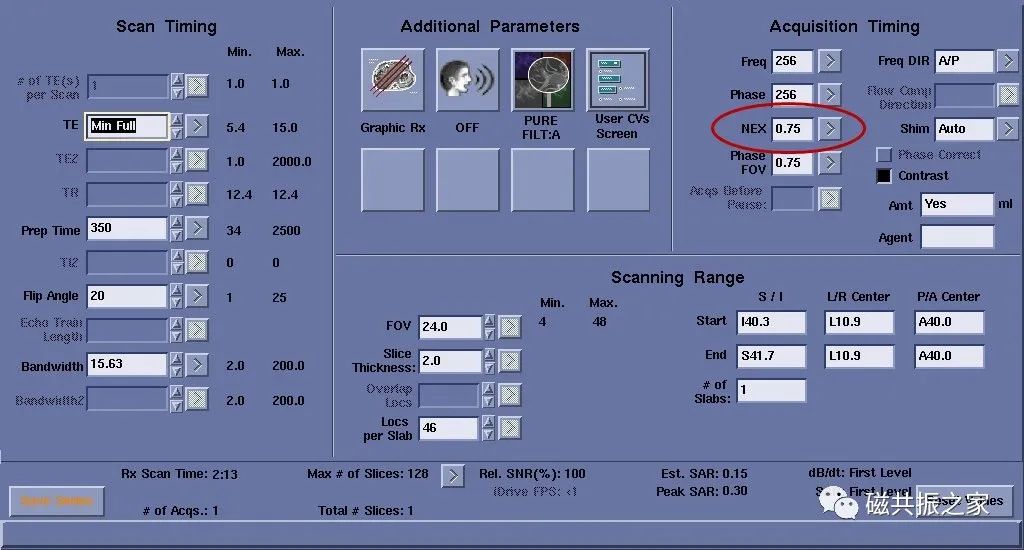

激励次数

图1,NEX为4时,扫描时间为1:52,图2,NEX为2时,扫描时间为1:05。NEX相对于其它参数来讲它们间的影响是最小的,NEX值最直接的影响的是信噪比与扫描时间,如将NEX由4改为2后,相对信噪比由图1的100% 变了图2的71%。

NEX一般设置是≥1的,但也有例外的,如采用相位部分傅里叶采集技术时可以小于1,如上图。

在一些快成像序列或3D薄层扫描中NEX常设置小于1以缩短扫描时间。